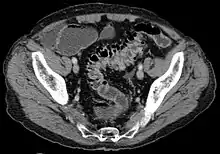

Imaging

- Contrast CT is the investigation of choice in acute episodes of diverticulitis and where complications exist.